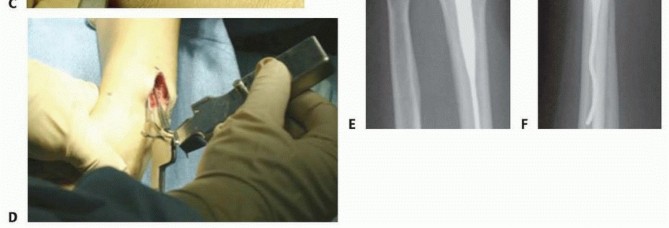

FIG 3 • A. PA radiograph (A) and lateral radiograph (B) of a healed distal radius fracture fixed with an intramedullary plate. C,D. PA and lateral radiographs showing an unstable metaphyseal distal radius fracture. (C,D: Copyright Thomas R. Hunt III, MD.)

SURGICAL MANAGEMENT Open reduction and internal fixation with a dorsal plate can be used successfully in the treatment of displaced, unstable, comminuted fractures of the distal radius that fail to respond to closed treatment. Dorsal plating buttresses the fracture to correct deformity and maintain fracture reduction. New intramedullary implants have been designed to alleviate some of the complications associated with traditional dorsal plates and allow a less invasive option for fixation of dorsally displaced fractures ( FIG 3A,B). Indications for plating include the following: Severe initial dorsal displacement ( >20 degrees from normal, ≥10 degrees dorsal tilt)10 Marked dorsal comminution (≥50% of the diameter of the radius shaft on the lateral radiograph) Residual (after reduction) dorsal tilt greater than 10 degrees past neutral Postreduction greater than 3 mm of radius shortening 10 Dorsal intra-articular fragment displacement or step-off of more than 2 mm 10 Stabilization using an intramedullary device is indicated for distal radius fractures without extensive articular involvement in which a limited incision and shorter procedure are desired (see TECH FIG 4E).3 Comminution of the volar metaphysis is a relative contraindication for the use of a dorsal intramedullary implant. Intramedullary fixation should not be used to treat marginal or sagittal shear-type intra-articular fractures or displaced fragments from intra-articular fractures. 3, 15 The surgeon should be prepared to change management intraoperatively and therefore, in advance of the procedure, must have additional stabilization options available such as percutaneous pins or an external fixator. ## Preoperative Planning All radiographic imaging must be reviewed before surgery. It is helpful to compare radiographs of the injured wrist to the uninjured wrist. Displaced intra-articular fragments must be identified and consideration given to the value of obtaining CT. Dorsal comminution must be evaluated to determine fracture stability and the need for bone grafting. The distal extent of the fracture must be determined to enable the buttress plate to function properly. Bone should be evaluated for osteopenia, osteoporosis, and tumors. ## Positioning The patient is placed supine on a regular operating table. A tourniquet is placed near the axilla with the splint in place. After anesthesia has been administered, the arm is placed on a radiolucent hand table ( FIG 4). Motion of the shoulder and elbow should be adequate to allow adequate reduction and positioning. Image intensification using fluoroscopy should be performed throughout the procedure to assess fracture reduction and the position of the hardware.

The tubercle of Lister is removed, and an awl is used to create an entry point in the dorsal cortex ( TECH FIG 4B). This usually involves a portion of the fracture line. The canal is rasped until the rasp may be fully seated ( TECH FIG 4C). The implant is placed using the insertion device to control rotation ( TECH FIG 4D). Typically, the fracture reduces as the device is inserted and seated due to the buttress effect and three-point fixation of the implant within the canal. Lag screws are inserted as required, followed by a cover lock to create fixed-angle stability. Reduction and stabilization are confirmed radiographically ( TECH FIG 4E,F). Wound closure and splinting are as described earlier.

C. A rasp is used to create a path for the implant. D. The implant is placed using the insertion device so as to control rotation during seating. E,F. An unstable metaphyseal distal radius fracture has been reduced and stabilized using a dorsal intramedullary device (Tornier Corp). (E,F: Copyright Thomas R. Hunt III, MD.)